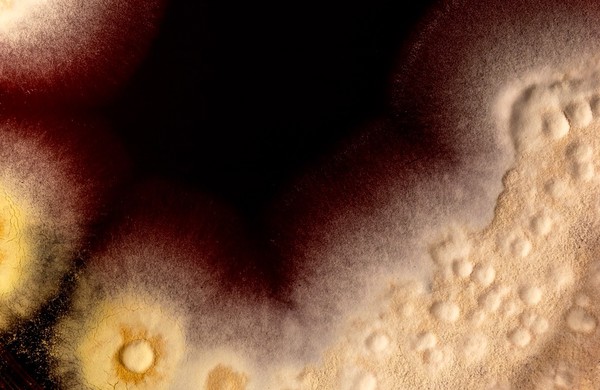

Bullous pemphigoid.